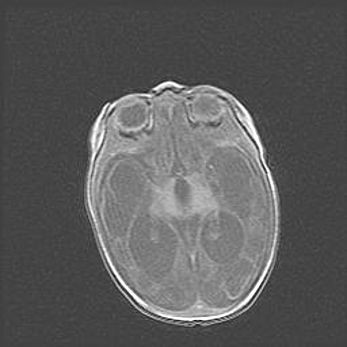

Церебральная ишемия II.

Возраст: 5 дней

Вес: 3400 г

Пол: женский

Окружность головы: 35 см

Срок гестации: 39 недель

Церебральная ишемия – это заболевание, характеризующееся недостаточностью (гипоксией) либо полным прекращением (аноксией) снабжения мозга кислородом по причине закупорки одного или нескольких сосудов. Это приводит к  что метаболическим расстройствам различной степени тяжести в тканях головного мозга, развитию коагуляционных некрозов и гибели нейронов.